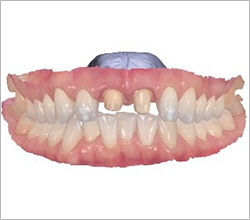

Full-mouth implants are highly advanced treatment that require precise upper and lower occlusal harmony. Patients themselves have proven us to be

a clinic specialized in full-mouth implant surgery.

Full-mouth implants are among the more complex dental procedures. They require careful decision-making, precise diagnosis based on each individual condition, and ongoing postoperative care after placement. With extensive experience in full-mouth implant treatment, Seoul The Nature Dental Clinic can provide systematic planning, placement, and follow-up care. Many patients continue to visit us through recommendations as a trusted clinic for full-mouth implants.